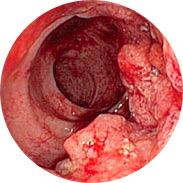

¿qué hace peligrosas las hemorroides en hombres y mujeres?

Inflamación e infección de la mucosa rectal

Inflamación e infección de la mucosa rectal El sangrado puede conducir al desarrollo de anemia

El sangrado puede conducir al desarrollo de anemia El aumento de la temperatura corporal, con inflamación severa, puede provocar fiebre

El aumento de la temperatura corporal, con inflamación severa, puede provocar fiebre ¡Y lo peor es el cáncer rectal!

¡Y lo peor es el cáncer rectal!